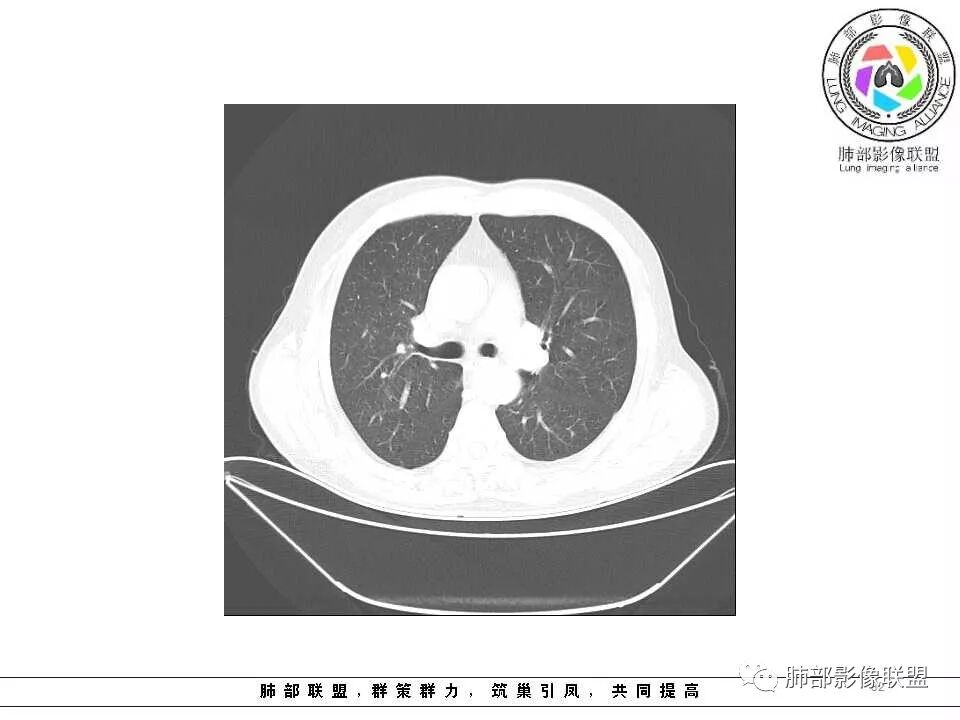

临床特点老年男性、有咯血一个月

影像学特点:肺气肿背景下在大概一年的时间里出现了一个光滑的小结节,因为图像给的不是太薄,与支气管的关系判断不清,从结节周围出现斑片状炎症来判断,应该考虑结节位于支气管内,周围是阻塞性炎症,这样比较容易解释咯血

纵隔窗上似乎结节内可见点状高密度影,同时没有明显肿大淋巴结

所以我考虑支气管内的恶性肿瘤,类癌可能大。

老年男性,左肺舌段见多个小结节灶及斑片状高密度灶、磨玻璃影,结节灶边界清晰,光滑,无明显分叶,密度均匀,周围病灶密度不均,一年内生长,考虑恶性肿瘤并阻塞性肺炎出血,小细胞可能大。

老年男性,肺气肿背景,左肺上叶舌段病灶明显增大,变异膨隆,远端阻塞肺炎,考虑鳞癌。

左肺上叶小结节病灶,形态规则,边缘光滑,密度至密,远处阻塞性肺炎,病灶与支气管关系密切,给图太少不好观察,考虑神经内分泌癌(类癌),其次鳞癌

左肺上叶光滑结节影 似乎与支气管没有关系  ,给的纵隔窗病灶中心似乎点状钙化  病灶旁有更小结节,与上一年片比较 结节增大明显  考虑恶性 类癌可能

老年男性,肺气肿基础。约一年时间出现左肺上叶舌段支气管近端结节影,远端斑片样阴影,边缘模糊。考虑近端恶性占位,远端有阻塞性炎症。

老年男性,两肺可见小叶中央型肺气肿,提示应该有抽烟史。2016年片,右肺门支气管稍模糊,考虑慢性感染,纵膈淋巴结稍大。但2017年左肺上叶新发占位,堵塞支气管,引起局部肺不张伴感染,且纵膈淋巴结较2016年变大,患者同时伴有咯血,考虑恶性。鳞癌?类癌?小细胞?

老年男性,有咳血病史,左肺上叶舌段一年时间出现新发类圆形小结节,感觉在支气管内,部分凸出气管外,没有mpr不好说,远端肺野斑片模糊影,考虑阻塞性炎症,纵隔无明显肿大淋巴结,小细胞代排,按照发展速度,类癌低度恶性,应该发展缓慢,一年病史,代排,首先考虑鳞癌并阻塞性炎症

肺气肿背景,2016年左肺上叶上舌段见微结节,2017年5月左肺结节增大,密度均匀,边缘光滑锐利,与邻近血管关系密切,血管贴壁走行,外侧见尖状突起,下舌段片状影,沿着支气管走行,内有粘液栓,考虑鳞癌,鉴别小细胞肺癌。

肺气肿背景,2016年左肺上叶上舌段见微结节,一年后左肺结节增大,密度均匀,边缘光滑、膨隆,似见小分叶,下舌段片状影,沿着支气管走行,内,老年患者,咯血1月。考虑恶性病变并阻塞性肺炎,鳞癌?注意鉴别结核。

左肺上叶舌段支气管管壁略增厚 间隔一年 管壁增厚明显 向腔外突出形成结节 管腔闭塞 远端片状及斑片影 纵隔淋巴结增大 肺气肿背景 考虑鳞癌伴阻塞性炎症可能

老年男性,咯血1月,肺气肿背景,16年左肺上叶舌段结节,左肺门疑似淋巴结肿大,呈结节感。17年左肺上叶舌段见沿支气管走行分布结节 远端阻塞性肺炎,左肺门淋巴结肿大明显,首先考虑恶性病变,鳞癌?类癌?

前次片2016年4月20相应位置就有小点状病灶,2017-5-15呈结节影改变,边界膨隆,远端阻塞炎性改变,考虑肺癌,鉴别炎性结节!

老年男性,肺气肿背景,左肺上叶舌段一年前小结节后长大,实性,与邻近气管关系密切,远端有少许小片状炎症类小结节状,左肺门淋巴结肿大,首先考虑恶性,鳞癌可能性大,代排小细胞癌。病灶下方斑片状影,考虑炎症。

老年男性,肺气肿背景,对比前片,左肺上叶舌段结节较前进展,周围有斑片状条状密度增高影,左肺门淋巴结肿大,有咯血史抗炎后效果不佳,目测增强强化不好判断,考虑肺癌并阻塞性肺炎可能,鉴别炎症性肺癌,真菌类肺炎,肺脓肿,肺结核,建议完善肿瘤标志物,结核相关检查,病原体检查。

老年男性,咯血一个月,有慢支病史。左肺上叶舌段可见一类圆形结节影,边缘光滑,远端有片条状影,一年前胸ct基本正常。感觉还是考虑肺癌合并阻塞性炎症。鳞癌还是小细胞?

老年男性,咯血1月,肺气肿背景,左肺上叶舌段见沿支气管走行分布结节,呈葫芦样改变,左肺门淋巴结肿大明显,首先考虑恶性病变,小细胞癌可能